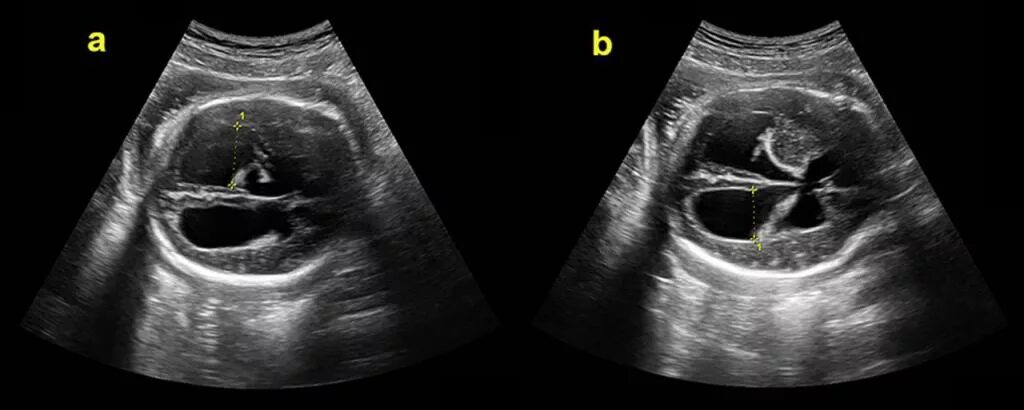

Узи шип